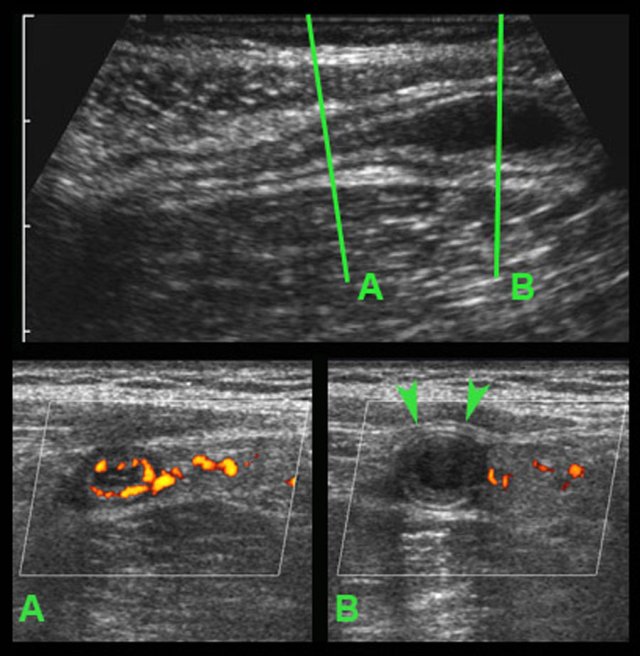

In this very lean patient with early acute appendicitis, US reveals dilatation of the distal appendix.

In plane A, Doppler US shows strong hypervascularization of the wall, however in plane B no vessels are visible in the appendix wall due to high intraluminal pressure.

Note the dilated, non-compressible, round appendix in B, bulging into the abdominal wall during compression (arrowheads), with only vascularization in the fatty meso-appendix.